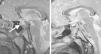

En el estudio realizado se detectan niveles de GH>40ng/ml, IGF-1 895,7ng/ml e IGFBP3 10,5μg/ml y la RM craneal muestra una fosa hipofisaria aumentada de tamaño, observándose una glándula que realza uniformemente con el contraste (fig. 1).

La campimetría y el fondo de ojo fueron normales. Ante estos hallazgos es diagnosticado de macroadenoma hipofisario productor de GH y es derivado al servicio de neurocirugía para resección mediante cirugía transesfenoidal.

Evolución favorable tras su extracción completa (figs. 1 y 2), con normalización de las cifras de GH (0,66ng/ml), IGF-1 (445ng/ml) e IGFBP3 (7,8μg/ml) un año después. Así mismo se objetiva un enlentecimiento del crecimiento (fig. 3); a los 6 meses se alcanza una talla de 192cm (p>99; 4,12DE), lo que implica una velocidad de crecimiento de 5,6cm/año (p<1; −2,48DE). No quedaron secuelas oculares y actualmente la función hipofisaria es normal.